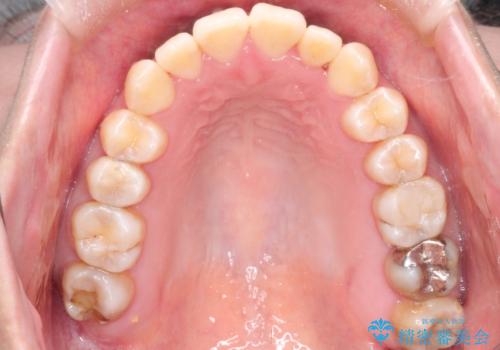

- 前歯のガタガタと、かみ合わせを改善したいとのことで来院されました。

人前でお話をするお仕事のため、装置をつけないでよいマウスピース矯正を希望されました。

下顎の歯が、上顎の歯に対して前方に位置していたので、下顎の歯を後方に移動させるのと、歯と歯の間を削りスペースを作り、歯を並べる計画としました。

お仕事の関係で使用時間が制限されるときもあり、治療期間が予想より少し長くなりましたが、装置をつけずに治療を終えることができました。